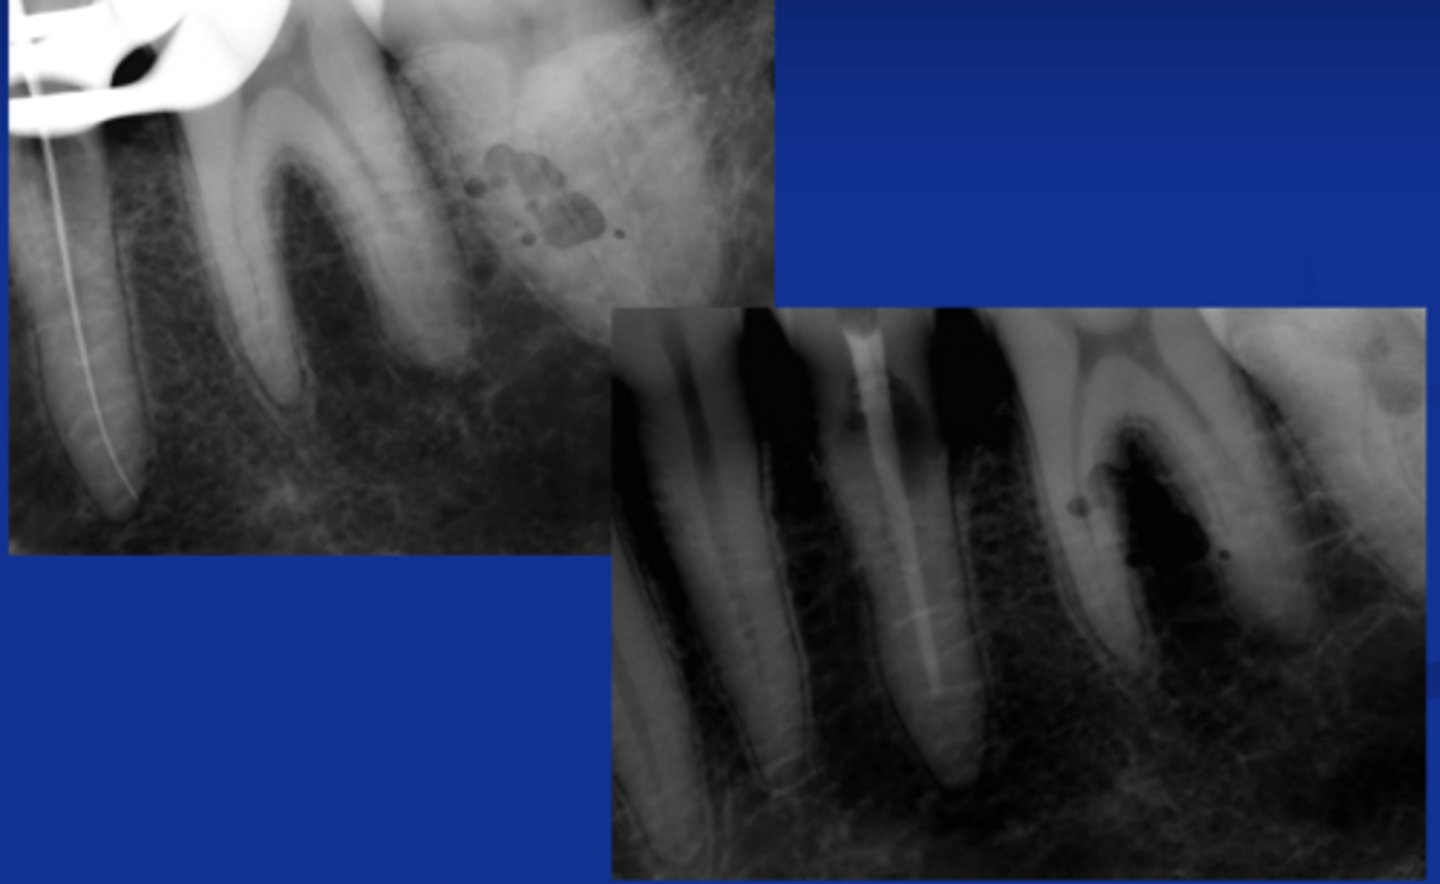

Infected silver point (Retreatment should be attempted first)

What is the cause of this apical radiolucency?

calcified/non-negotiable canal